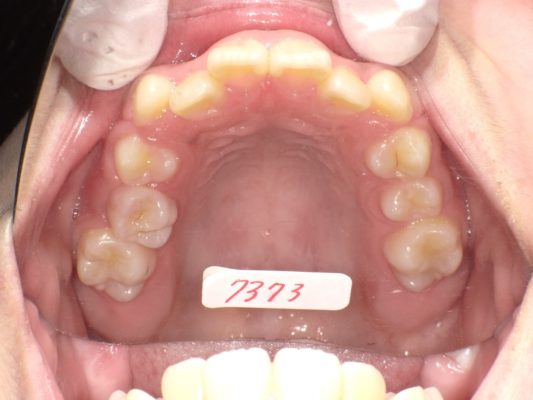

(主訴)一番気になるのは、反対咬合。他は、可能な限り治療をお願いしたい。

- 上顎左右側切歯矮小歯(わいしょうし)は、あまり気にならない。

(所見)

手根骨X-p成長期にあります。(軟骨あり)

パノラマX‐p所見

左側上下智歯(親知らず)あり、右側は上下とも無し。今後できる可能性あります。智歯が出来た状態で生え方に異常があれば、大学での抜歯が必要な場合もあります。その時は、別途 1本約15,000円位負担になります。上顎左側第二小臼歯捻転し、生える場所が不足気味です。全ての永久歯はあります。